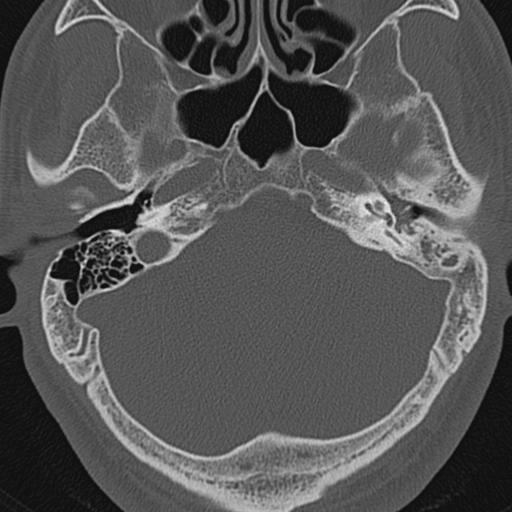

以下是引用zxl51642在2009-8-25 13:37:00的发言:[br]1、左侧慢性硬化型中耳乳突炎(中耳鼓室腔及听小骨受累),并胆脂瘤形成;2、左侧外耳道软组织密度影填塞,考虑炎性肉芽肿,建议结合临床;3、右侧颈静脉窝较左侧明显扩大,不排除颈静脉球瘤,建议mr进一步检查。

以下是引用随光逐影在2009-8-25 19:05:00的发言:[br]1)左侧慢性中耳乳突炎(肉芽肿或胆脂瘤形成),左侧外耳道炎性肉芽肿。2)右侧颈静脉球高位。